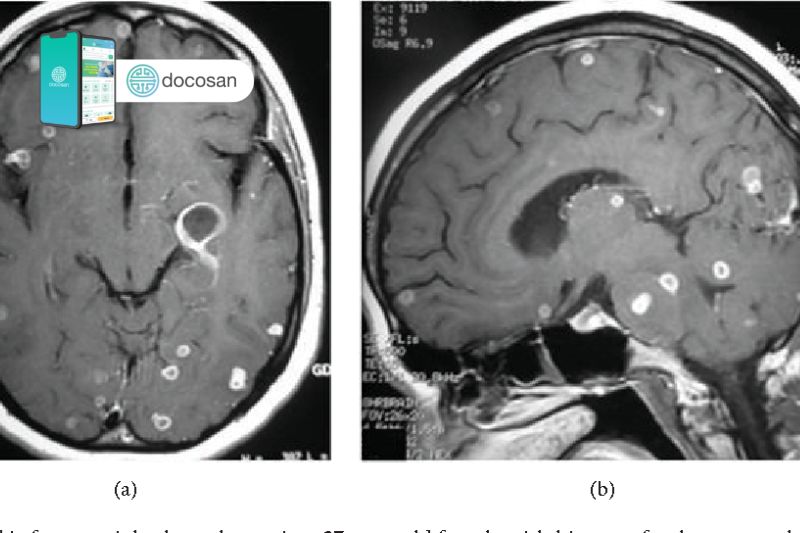

Lao ở màng não là một bệnh lý lao nặng và đặc biệt nguy hiểm, nếu không điều trị thì nguy cơ tử vong gần như là chắc chắn hoặc điều trị muộn, điều trị không hiệu quả sẽ để lại những di chứng nặng nề. Người bệnh có thể mắc lao màng não, thậm chí u lao nội sọ và viêm lao màng tủy sống hay lao màng nhện tủy sống.